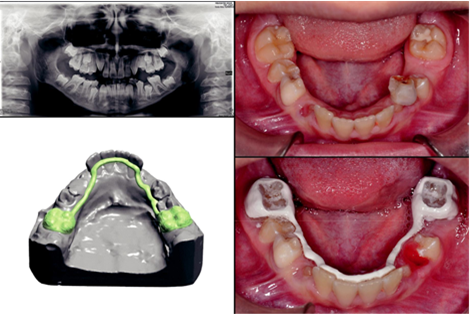

Figure 1 & Figure 2 are indicated artificial hip and knee joints implanted in humans. In hip joint acetabular metal, in Liner ceramic, Femoral Head ceramic, and Femoral Stem metal are used. Cartilage works mostly between Femur and Tibia, mainly on slippery, friction, and wear. Cartilage is connected to Femur and tibia by cross-linked joint. Due to movement of the body i.e. Tibia and Femur, there is a lot of pressure on the cartilage. The main reason for being wasted in cartilage is because of a road accident, sports accidents, carrying heavy things, and getting older. If a bone contacted to cartilage is lost due to accidental or other reasons, it may cause pain when it turns fracture with cartilage after some time, by replacing the bone with bio-materials or materials. Most of the bones next to cartilage are changed with different types of materials such as alumina, cobalt-chromium, titanium alloy, stainless steel, and ultra-high polyethylene, etc. This material is much more of the hardness and strangulation which is very much needed. These materials are very easy to find, and they are quite cheap at prices. The hip joint consists of the cross-linked of the femoral head and acetabulum cup. Figure 5 shows that metal ions are emerging and entering the joint space. These ions are interrupted with side tissues and capsules in Figure 6. Those who have to fall in front of the damage to the body, in addition to their hip substitution (also called add up to hip arthroplasty), the harmed bone and cartilage is evacuated and supplanted with prosthetic components. The harmed femoral head is evacuated and supplanted with a metal stem that's set into the empty center of the femur. The femoral stem may be either cemented or "press-fit" into the bone. A metal or ceramic ball is put on the upper portion of the stem. This ball replaces the harmed femoral head that was removed. The harmed cartilage surface of the attachment (acetabulum) is evacuated and supplanted with a metal attachment. Screws or cement are in some cases utilized to hold the attachment in place. A plastic, ceramic, or metal spacer is embedded between the unused ball and the attachment to permit a smooth floating surface. Currently, there are many types of design and metal used in artificial hip joints. Two types of common components are seen: (1) Ball component (2) Socket component. Ball component is usually highly polished metal or ceramic material. And socket component is sturdy plastics or ceramic, metal. The impacts of mental flotsam and jetsam discharged from prosthetic hips incorporate component releasing, component misalignment, contamination, bone breaks, disengagement, metal affectability, and noteworthy torment. Other issues incorporate delicate tissue devastation which may compromise corrections and amendment surgery. In mal arrangement, specific surfaces are pounding despicably which causes metal parts and particles to discharge and enter into encompassing tissues and joint spaces. These wear flotsam and jetsam may moreover contribute to aggravation in adjoining tissues and systemically all through the body. The main reason for using cobalt-chromium is a good surface finish, availability, and lower friction. Dental bio-tribology is a developing and promptly expanding research field that develops an understanding for designing dental implants and a better selection of artificial dental material. The importance of tribology in modern restorative dentistry is significantly reviewed including synthetic teeth and dental implants. In dentistry, filler materials are used like metal, alloy, and ceramic also. Crown materials mainly ceramic, metal, and composites are recommended. Polymer materials are mainly used as adhesive. These are also used in other prostheses and retainer. These figures' mechanisms mainly help the baby's tooth straighten out in a time of toothache (Figure 7).

Figure 7 Polymer in orthodontics.63